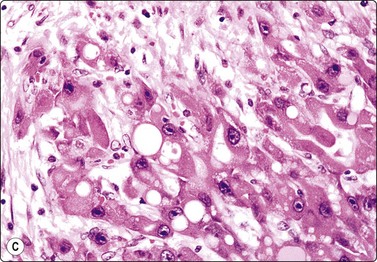

Metastatic malignancy (Figs 10.31 and 10.32)

The liver is a common site of metastatic disease because it acts as a filter. Differentiation between primary and secondary tumors on imaging can be problematic. The differential diagnosis between primary hepatocellular carcinoma and metastatic malignancy and the use of immunostaining to discriminate between them has been previously discussed in the section on HCC. Metastatic tumors may be single, multiple or diffusely infiltrating. The metastatic deposit usually shows the morphological characteristics of the primary tumor. Clinical history is very important in making the diagnosis. Review of any previous histology or cytology is recommended.

image

Fig. 10.32 Liver metastasis of colorectal carcinoma

Columnar cells arranged in glandular formation on a background of granular debris (Pap, HP).

The clinician needs to know whether liver involvement is present, either from a primary tumor which has already manifested or one which is still occult. The result of FNA will often dictate management such as chemotherapy.211 Cell typing is thus desirable in most instances. We regard it as particularly important to identify accurately those metastases which are potentially chemosensitive or hormonally manipulable. It is useful to run through a mental checklist to ensure that one is not missing germ cell tumors, neuroendocrine tumors (including small cell undifferentiated carcinomas) or carcinomas of breast, prostatic, endometrium, thyroid or even nasopharyngeal origin.

The macroscopic appearance of the aspirate is usually quite different from that of normal liver tissue. There is frequently less admixture with blood and often a high cell content. The aspirate is easily smeared into a grayish film. Necrosis may be pre-eminent, sometimes to the extent that preserved, diagnostic cancer cells are hard to find. A necrotizing metastatic tumor deposit may present as a cyst.87 If hepatocytes are found amongst the neoplastic cells, they provide a useful baseline for the evaluation of cell and nuclear size.

The cytologic patterns of metastatic carcinomas and clues to the identification of the primary site of origin are described in Chapter 5 and will not be repeated at length here. Adequate sampling is the key. Colonic adenocarcinoma is probably the most common source of liver metastases. The cytological pattern is characteristic, showing malignant columnar epithelial cells in palisaded rows or microglandular groups with a background of necrotic debris (Fig. 10.32), often with evidence of mucin secretion.35 Small cell undifferentiated carcinoma of pulmonary or colonic derivation often involves the liver diffusely. Hepatocytes may be numerous and evenly dispersed between tumor cell groups in smears. Hepatic FNA in these cases has staging value in anticipation of chemotherapy.212 Carcinoid tumors of bronchogenic, pancreatic or colonic origin are distinguishable from metastatic adenocarcinoma by their endocrine appearance. The nuclei have a rounded shape with ‘speckled’ granular, hyperchromatic chromatin. Red (MGG) cytoplasmic granularity may be visible. The diagnosis can be confirmed by immunoperoxidase staining for neuroendocrine markers.213